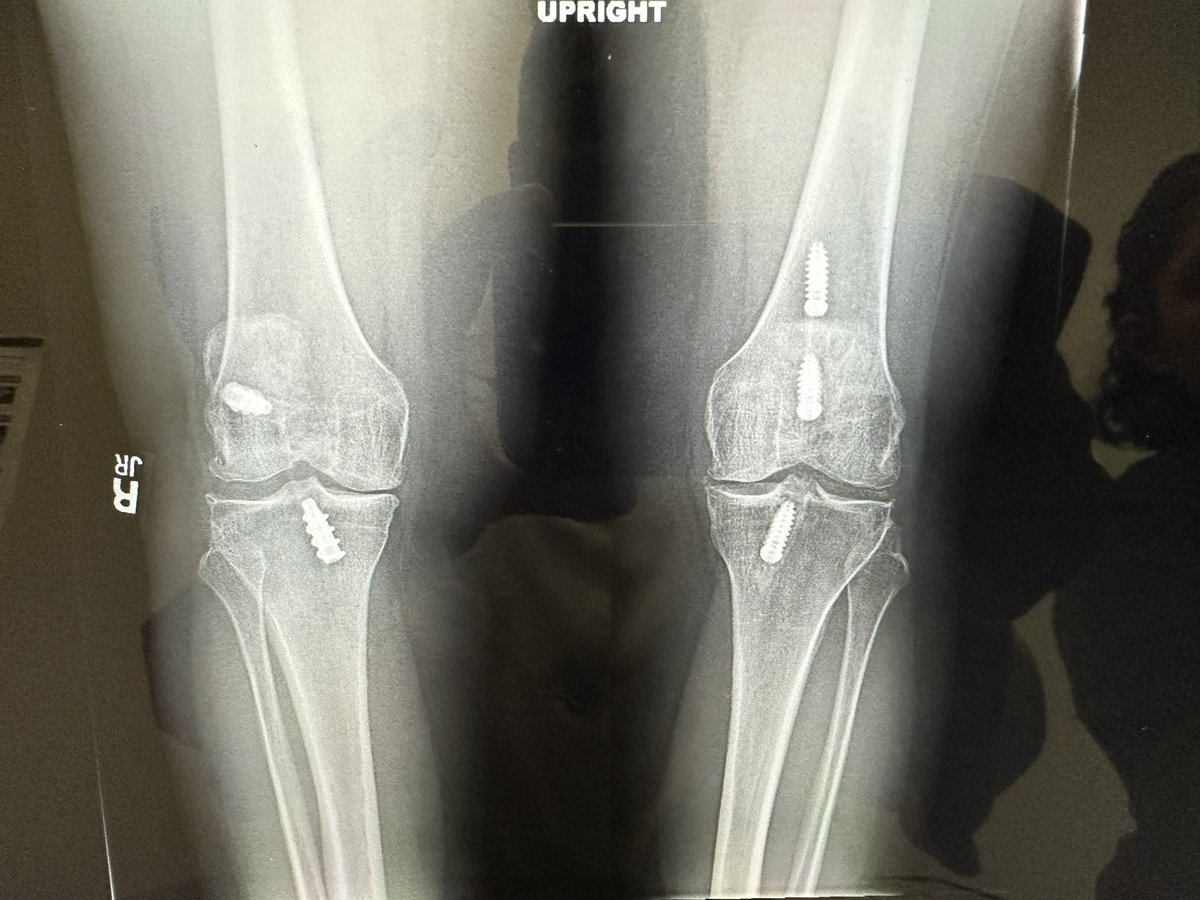

#orthotwitter Help me make some sense of these left knee X-rays Single left knee ACL reconstruction with allograft in the 1990s. That’s all I got.

#orthotwitter

Help me make some sense of these left knee X-rays

Single left knee ACL reconstruction with allograft in the 1990s. That’s all I got.